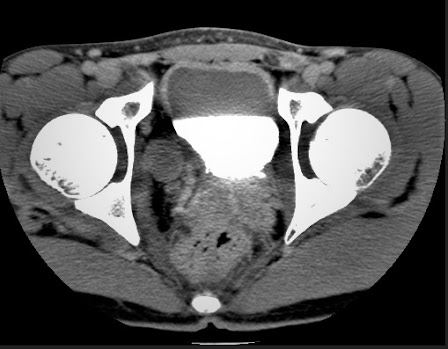

Ewing sarcoma

ReplyDeleteTunred out to be PNET on histopathology.